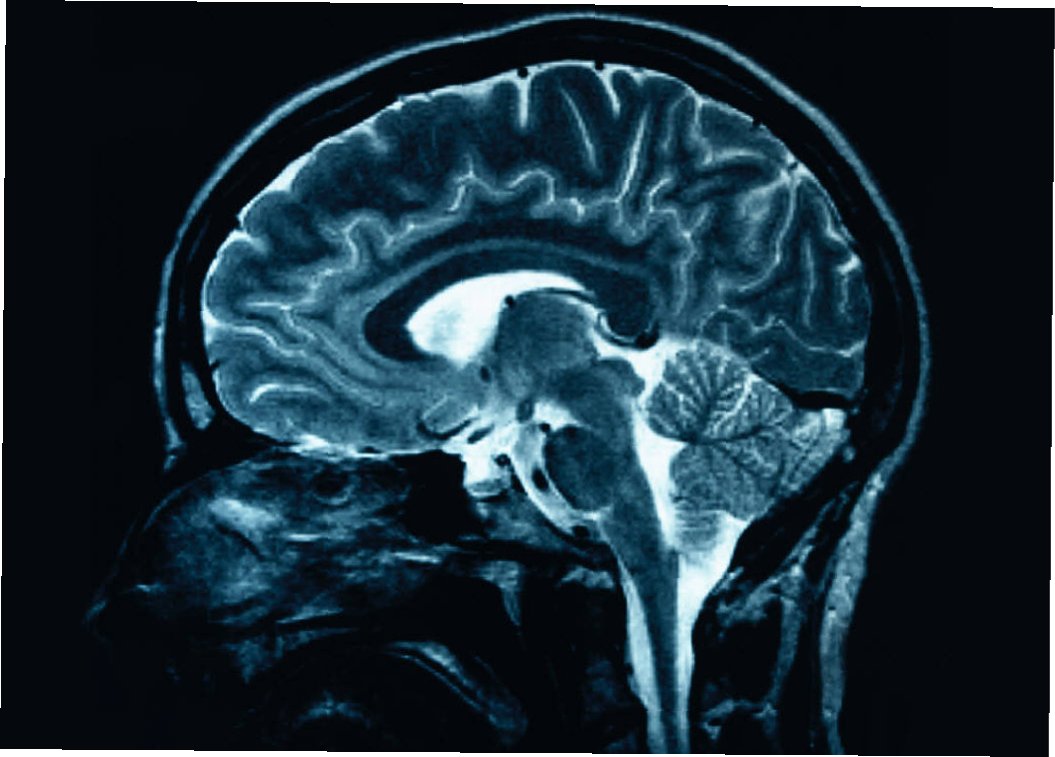

뇌전증의 진단은 신경학적 검사, 뇌파 검사(EEG), 뇌 영상 촬영(MRI, CT) 등을 통해 이루어집니다. 뇌파 검사는 뇌의 전기적 활동을 기록하여 발작의 특징을 파악하는 데 도움을 줍니다. 뇌 영상 촬영은 뇌의 구조적 이상을 확인하고 뇌전증의 원인을 찾는 데 사용됩니다. 뇌전증 치료는 약물 치료가 기본이며, 발작 조절을 목표로 합니다. 약물 치료에 반응하지 않는 경우, 수술적 치료나 신경 자극술을 고려할 수 있습니다. 뇌전증 환자는 규칙적인 생활 습관을 유지하고, 스트레스를 관리하며, 발작을 유발할 수 있는 요인을 피하는 것이 중요합니다. 뇌전증 환자는 정기적인 진료를 통해 질병의 경과를 관찰하고, 부작용을 관리해야 합니다.